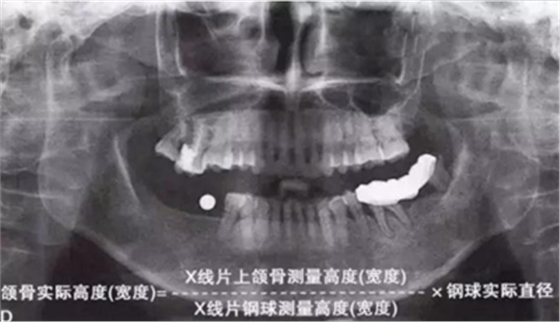

如何通過(guò)曲面斷層片測(cè)量出相對(duì)準(zhǔn)確的數(shù)據(jù)?告訴大家一個(gè)很實(shí)用的方法,就是利用小剛球作為參照。

將小剛球放到口內(nèi)時(shí)拍攝曲面斷層片,拍攝后得到的結(jié)果就是這個(gè)樣子的:

因?yàn)樾偳虻闹睆绞枪潭ǖ?,通過(guò)測(cè)量片子上小剛球的直徑,就能算出曲面斷層片的放大率,然后就能算出真實(shí)的骨高度了,這是一個(gè)很不錯(cuò)的方法。